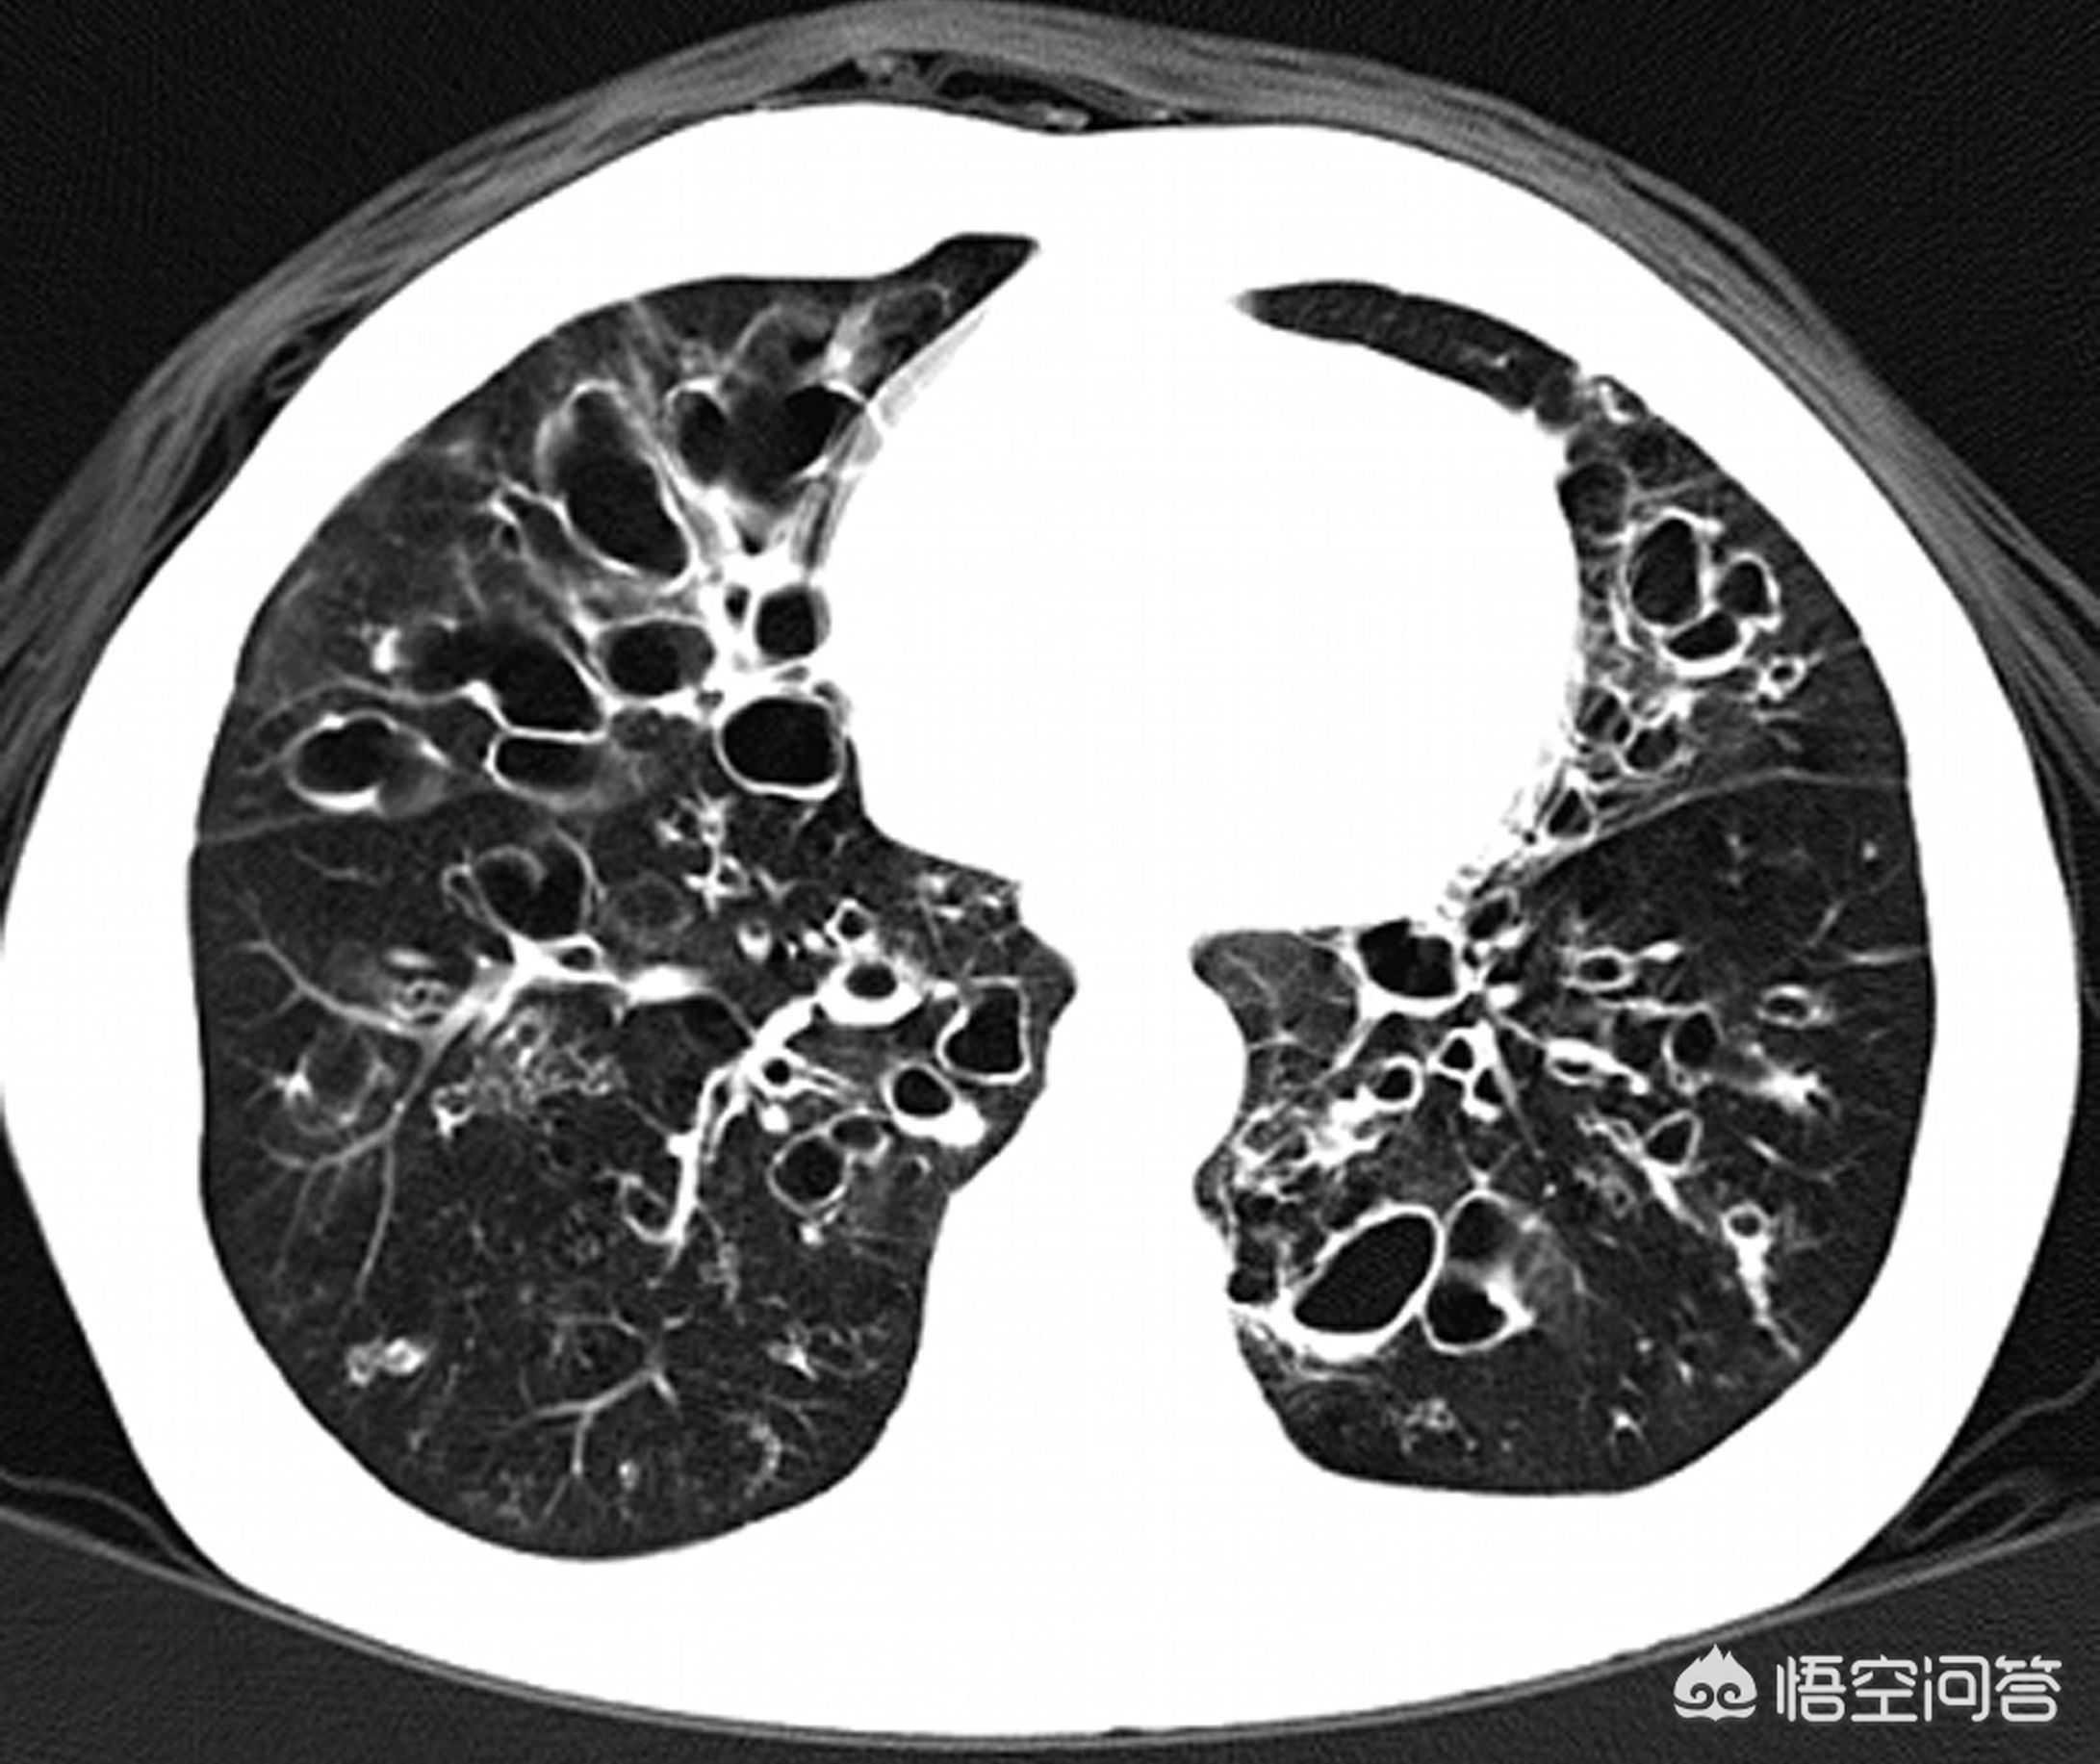

支气管扩张是一种结构破坏性疾病,通常是由于感染,有些是因为创伤,造成肺部特别是支气管管壁以及周围支撑组织损伤破坏而引起,还有一些是先天性疾病引起,比如纤毛不动综合征,幼年起就容易感冒咳嗽发热,逐渐形成支气管扩张,同时伴有特征性的内脏范围,不孕不育。支气管扩张分为局限性支扩和弥漫性支扩,局限性支扩相对症状较轻,可以通过手术根治,弥漫性支扩则症状持续,并进行性加重,只能通过药物等方法控制症状。

双下肺弥漫性支扩的患者则容易病情不断发展并且自我加重,这主要和痰液淤积不容易排出有关,支扩的患者管壁遭到破坏,局部免疫力随之崩塌,管壁表面的一些扮演搬运工角色的结构——纤毛不能正常工作,大家知道,气管壁表面细胞都长有头发也就是纤毛,这些纤毛可以向着咽喉部一起摆动,这样就能够把每天分泌的粘液排出,但支扩患者这方面功能受损导致粘液不断淤积,而肺又是和外界相通的,吸进来的细菌本应该被正常的免疫系统清除,在支扩患者身上则会迅速的定植到粘液中,并吸收粘液中丰富的蛋白质而生长形成感染并进一步破坏支气管,这就是支扩自我加重的原因。由于下肺支扩患者无法自我排出痰液所以必须借助于体位引流排痰,我之前多次科普过体位引流排痰的方法,经典的姿势是像青蛙一样趴在床上,头低屁股高家人帮忙拍背,将痰液缓慢咳出,每天十五分钟可以保持支扩病情稳定。